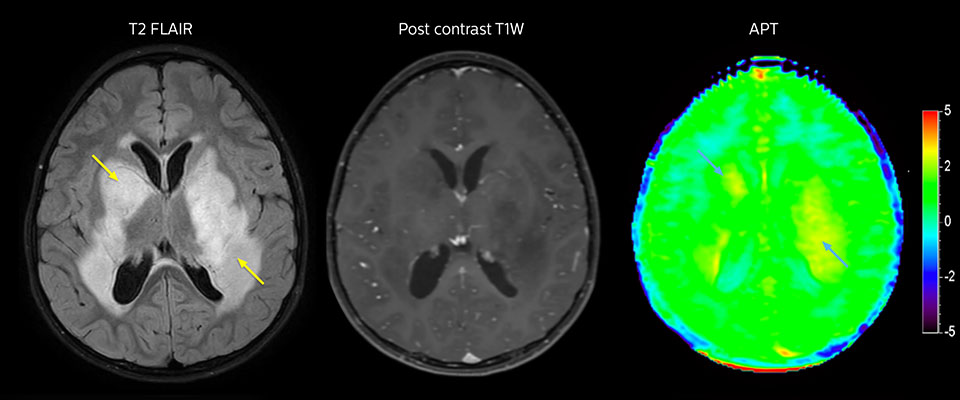

Low-grade glioma in a 5-year-old patient with neurofibromatosis 1. This low-grade lesion does not enhance on the post-contrast images, but does show an intermediate APT signal. The lesion stability over time confirms that it is a low-grade pathology.